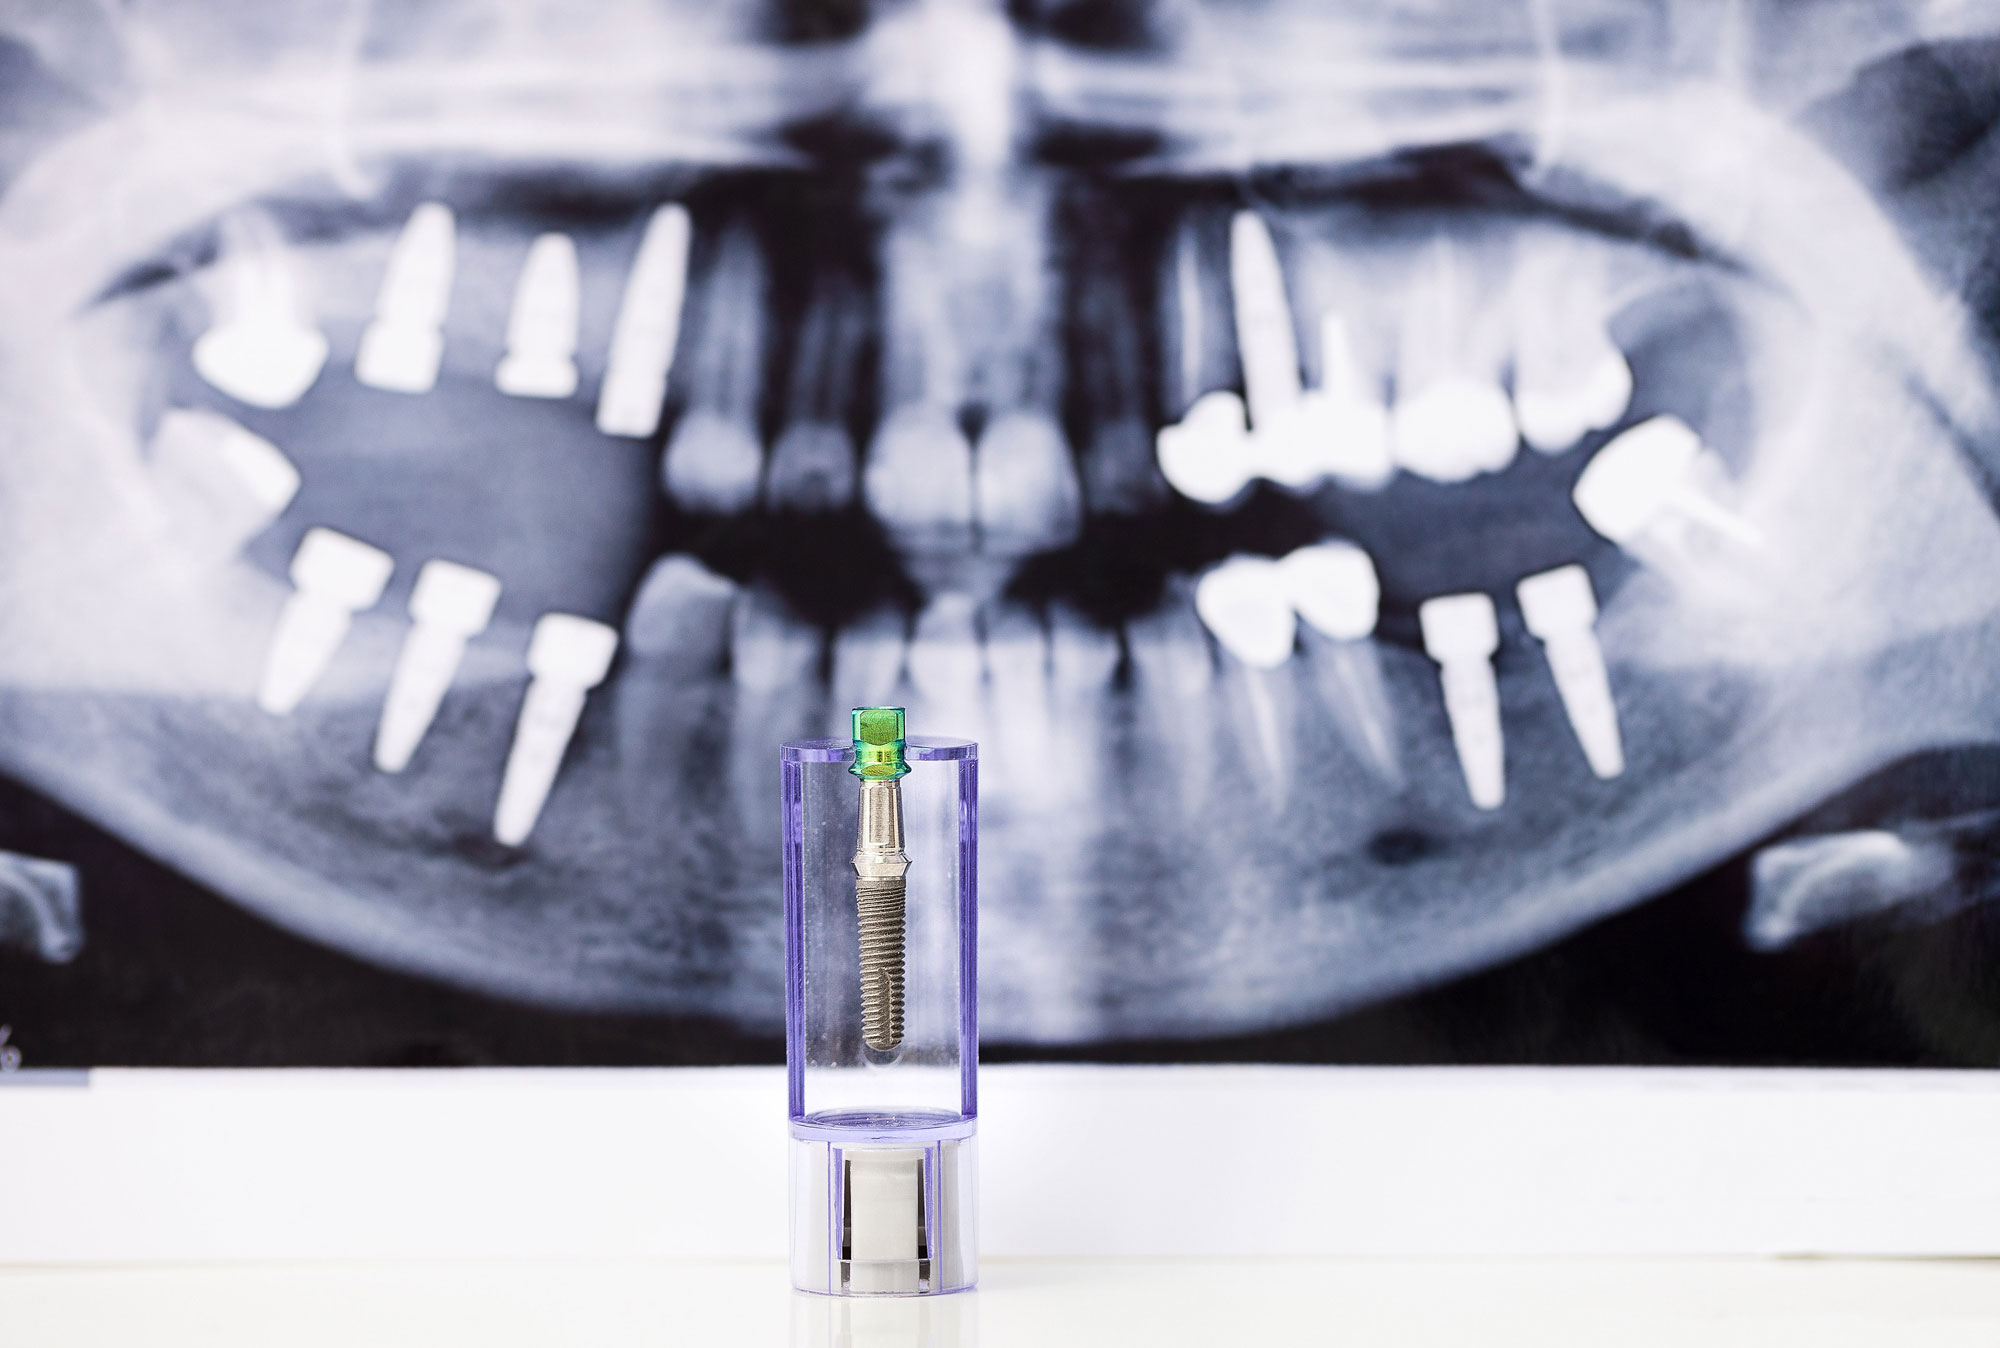

Die festsitzende Zahnversorgung, wie zum Beispiel Brücken, Kronen

Bei größeren Defekten und einzelner fehlender Zähne, kann festsitzender Zahnersatz in Form von Kronen und Brücken notwendig werden.